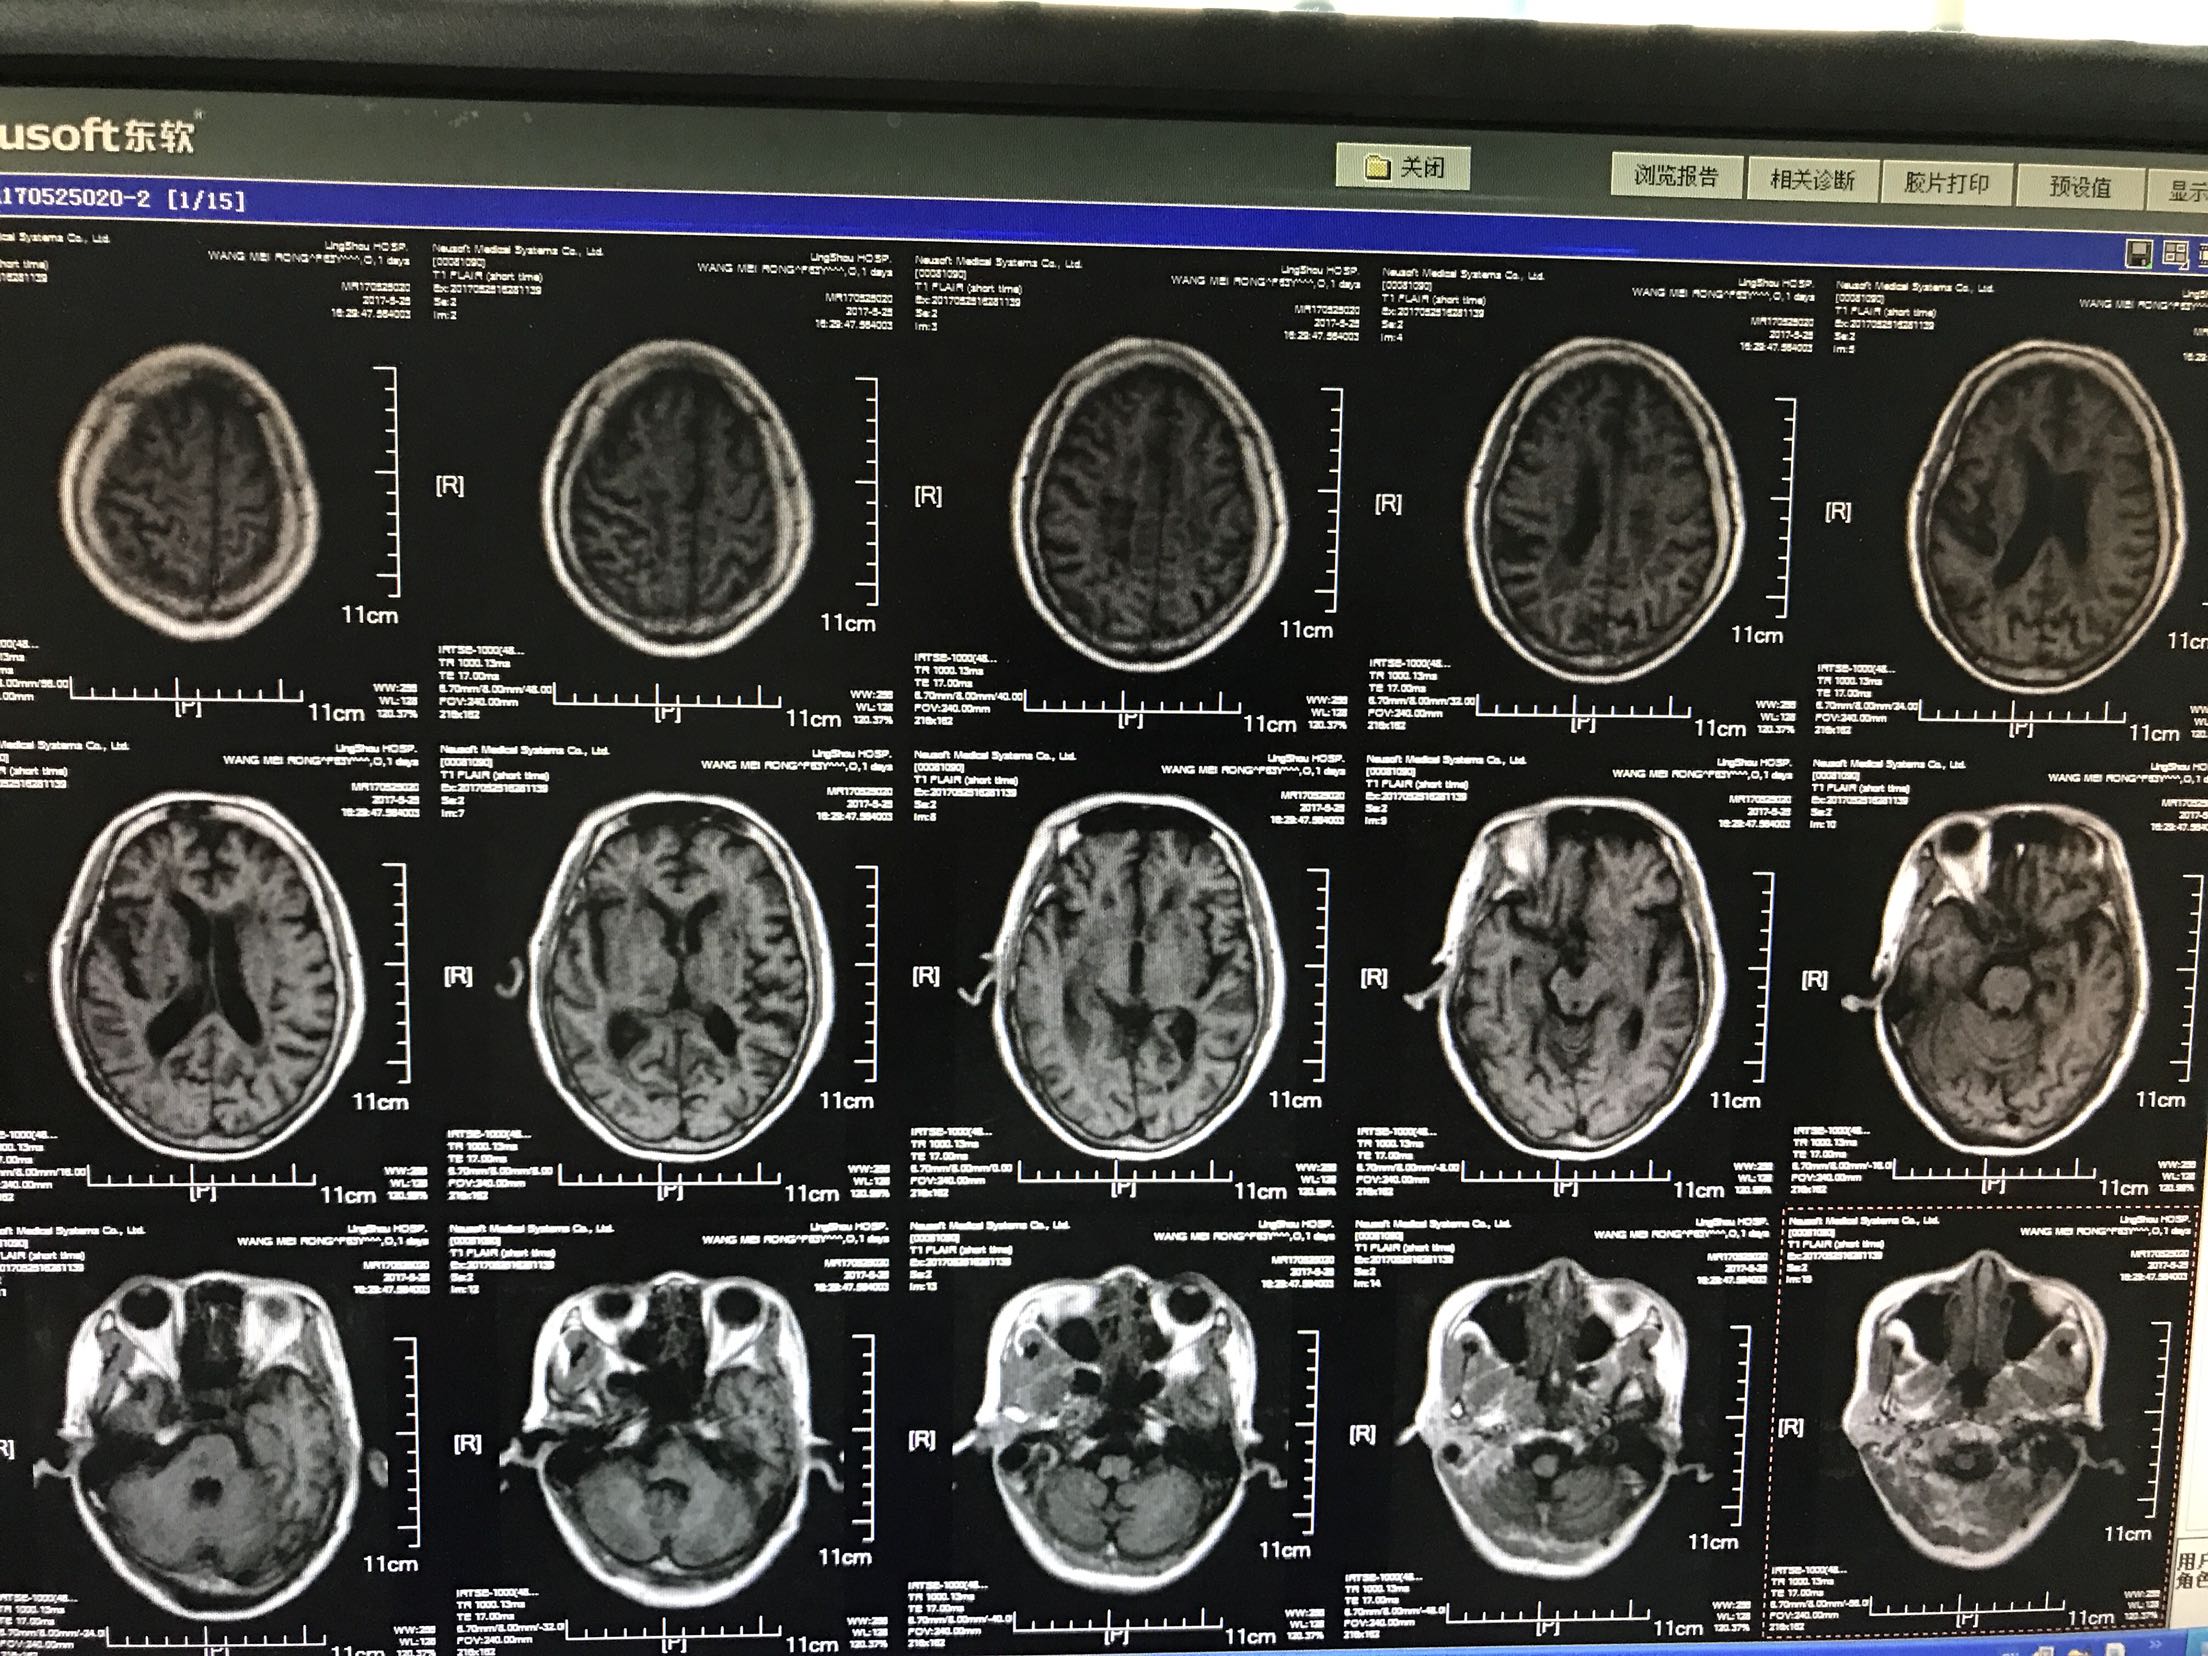

左侧肢体无力加重4小时入院,患者老年女性64岁,既往脑梗死病史10年,长期口服"阿司匹林",曾服用阿托伐他汀,后自行停服!留有左侧肢体无力后遗症,"糖尿病病史"5年,平素不规律服用"二甲双胍缓释片和消渴丸"。自诉血糖控制不佳,有夜间发生低血糖!"高血压"病史5年,长期口服氨氯地平片,具体血压控制不详。患者4小时前无明显诱因出现。左侧肢体无力加重,左上肢可以抬举持物,左下肢尚可负重,能独立行走,急诊查核磁示"脑梗死",收住院

体温37.5℃脉搏95次/分,呼吸22次/分,血压135/87mmhg,神情,言语基本流利,眼动充分,无明显眼震,伸舌居中,颈无抵抗,双肺呼吸音清,未闻及干湿性啰音,心音低钝,心律规整,未闻及杂音,双上肢肌力3级,肌张力增高,左上肢屈曲,双下肢肌力2级肌张力了,左巴氏征阳性,右巴氏征阴性,克氏征阴性,

1.脑梗死2.2型糖尿病3.高血压4.脑梗死后遗症,给于阿司匹林及波立维抑制血小板聚集,短效胰岛素控制血糖,阿乐稳定动脉板块,低分子肝素钙抗凝,降纤酶及脑苷肌肽等静点